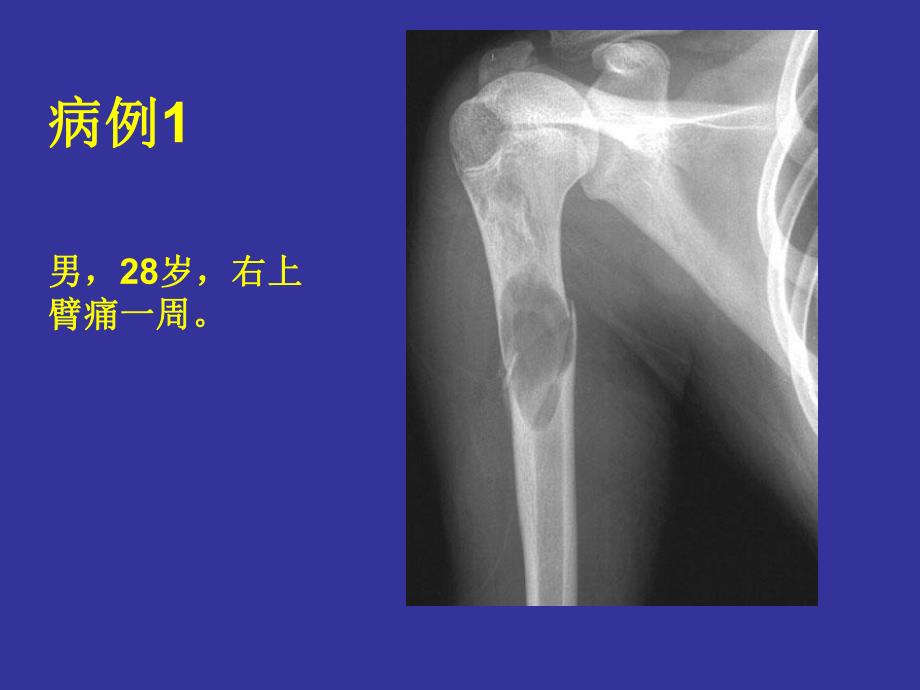

1、骨囊性病变骨囊性病变 骨囊性病变大部分是由良性骨肿瘤骨囊性病变大部分是由良性骨肿瘤及肿瘤样病变所引起,少数可能与炎及肿瘤样病变所引起,少数可能与炎症和外伤有关。平片表现为单发或多症和外伤有关。平片表现为单发或多发圆形、椭圆形或不规则形骨破坏区。发圆形、椭圆形或不规则形骨破坏区。病例病例1男,男,28岁,右上岁,右上臂痛一周。臂痛一周。手术病理证实为骨囊肿。手术病理证实为骨囊肿。骨囊肿好发于长骨干骺端,尤以股骨及骨囊肿好发于长骨干骺端,尤以股骨及肱骨上端。肱骨上端。X线表现:呈卵圆形或圆形、边线表现:呈卵圆形或圆形、边界清楚的透光区,其内可见横行骨嵴。囊界清楚的透光区,其内可见横行骨嵴。囊肿沿长